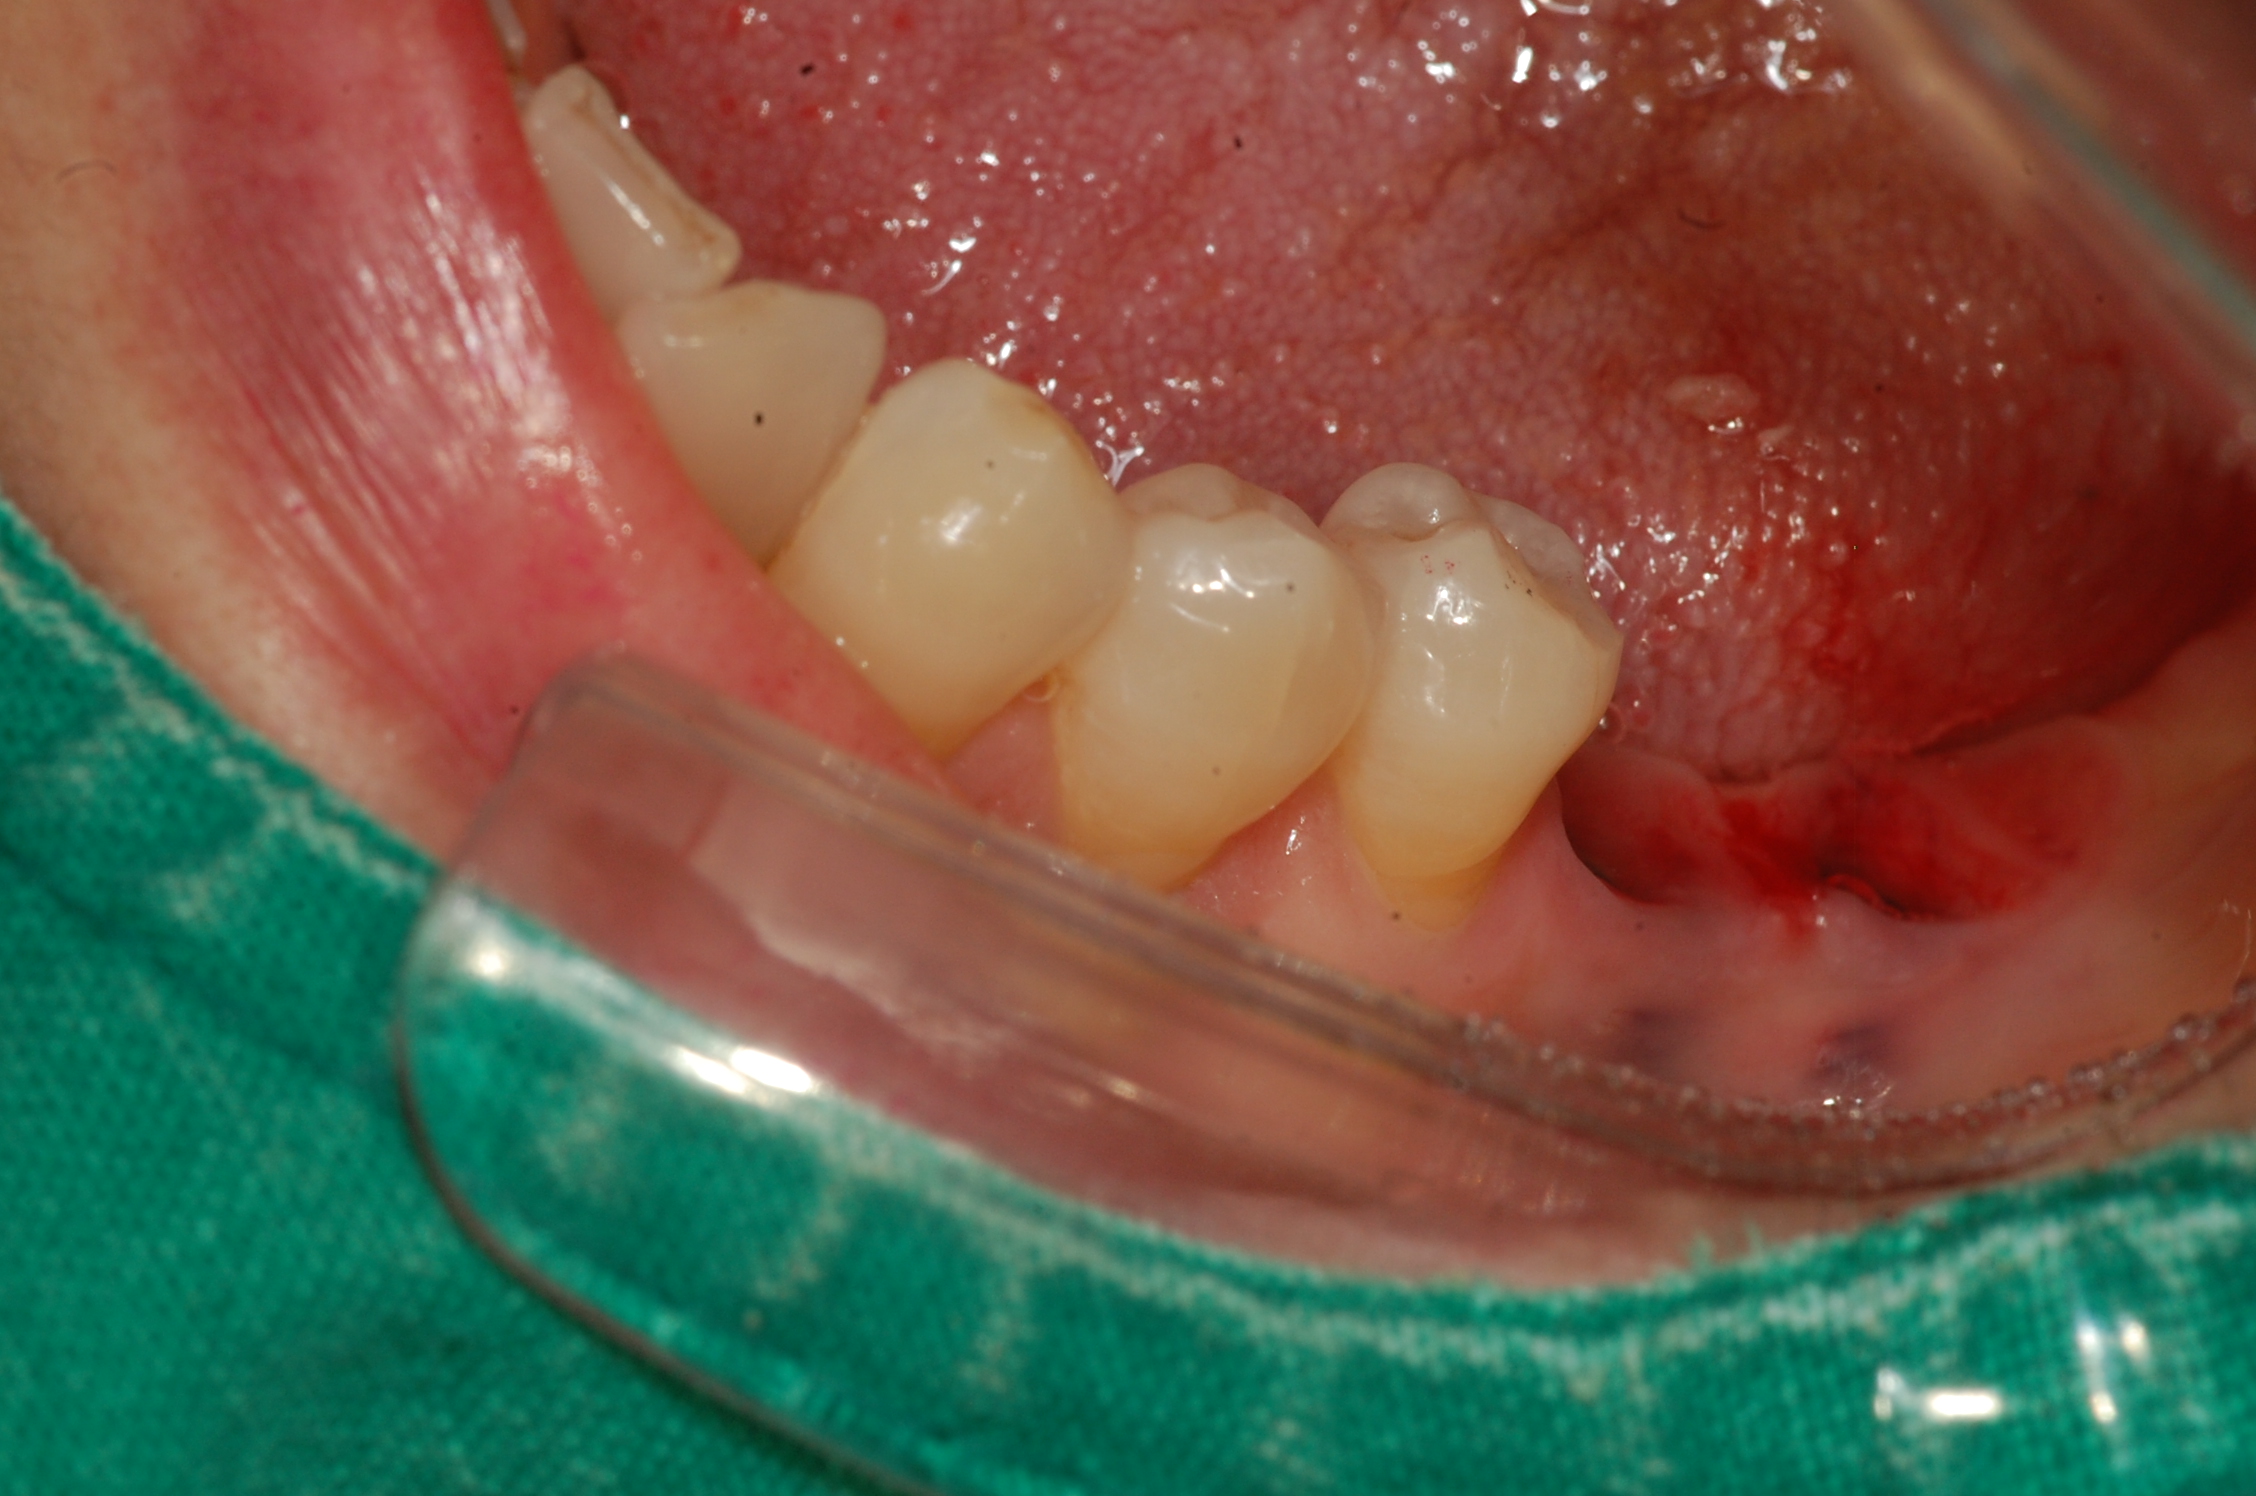

[임플란트] 제목 : 임플란트 지르코니아 보철

구치부 임플란트의 지르코니아 보철 치료 예입니다.